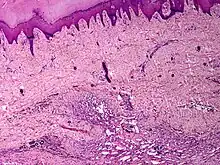

Skin angiomatosis

Angiomatosis is a non-neoplastic condition[1] characterised by nests of proliferating capillaries arranged in a lobular pattern, displacing adjacent muscle and fat.[2] It consists of many angiomas.[3]

These tend to be cavernous hemangiomas, which are sharply defined, sponge-like tumors composed of large, dilated, cavernous vascular spaces.

It is a vascular malformation wherein blood vessels proliferate along with accompanying mature fat and fibrous tissue, lymphatics and sometimes nerves.[2] They may involve skin, subcutaneous tissue, skeletal muscle and occasionally bone.[2]